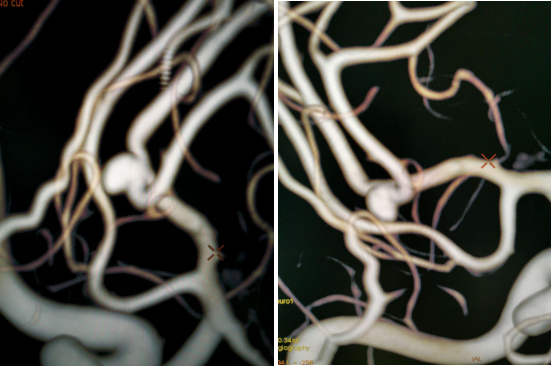

全脑血管造影:右侧大脑中动脉M1分叉处动脉瘤,瘤体3.3 mm*4.1 mm,瘤颈2.7 mm。前交通动脉瘤栓塞完全。

全麻满意后,常规消毒铺巾,采用改良 Seldinger技术穿刺右侧股动脉成功,置入6F动脉鞘。黑泥鳅导丝带领5F单弯导管行脑动脉造影,右侧颈内动脉造影见:右侧大脑中动脉M1分叉处动脉瘤,瘤体3.3 mm*4.1 mm,瘤颈2.7 mm。前交通动脉瘤栓塞完全。

经右侧股动脉鞘,黑泥鳅导丝带领导引导管(Codman 6F Envoy DA)到达右侧颈内动脉岩段,微导丝(Synchro--14 0.014 in*200 cm)带领支架微导管(Excelsior SL--10)到达右侧大脑中动脉M2段,退出微导丝。微导丝带领弹簧圈微导管(Echelon10)到达右侧M1远端分叉处动脉瘤内,退出微导丝。经弹簧圈微导管填入弹簧圈(Codman 3 mm*4 cm)经支架微导管输送支架(Neuroform Atlas 3.0 mm*15 mm)并释放在M2段至M段中部,完全覆盖动脉瘤颈。继续经弹簧圈微导管依次填入弹簧圈数枚,间断造影确保右侧大脑中动脉及远端血流通畅。右侧颈内动脉造影确认:动脉瘤致密填塞,载瘤动脉通畅,手术结束。有侧股动脉穿刺处用血管封堵器封堵,并压迫器持续压迫。术后患者麻醉清醒,拔除气管插管,呼唤应答,对答切题,言语清楚,四肢肌力肌张力正常。安返病房。

患者在全麻下、多参数监护仪监测下行前交通动脉瘤经右侧颈内动脉支架辅助下栓塞术。全麻后,常规消毒销巾,采用改良seldinger技术穿刺右侧股动脉或功,置入6F动脉鞘。黑泥鳅导丝及多功能导管带领6F MPD导管达到右侧颈内动脉岩段,行造影见∶前交通动脉瘤,瘤体3.5 mm*5.1 mm。在路图引导下,徵导丝(Synchro 0.014 in*200 cm)带领弹支架微导管(SL-10)到右侧大脑前动脉A2段,退出微导丝。微导丝(Synchro 0.014 in*200 cm)带领弹簧圈微导管(eV3 Echelon-10)到达前交通动脉瘤体内,退出微导丝。经弹簧圈微导管填入首枚弹簧圈(Codman COMPLEX XTRASOFT3 mm*6 cm)成篮良好,在路图引导下在支架管内输送支架(Neuroform Atlas 3.0 mm*21 mm)并释放完全覆盖动脉瘤颈,造影可见支架打开良好解脱首枚弹备圈,沿弹簧圈导管继续填入弹簧圈(可见护理记录单)间断造影确保双侧大脑前动脉血流通畅。右侧颈内动脉造影确认∶前交通动脉瘤填塞致密,双侧大应前动脉血流通畅。手术结束。右侧股动脉鞘处用血管封堵器(Coxrds Exoseal 6F)封堵,并压迫器持续压迫。木后患者清醒。

Neuroform Atlas支架系统是Neroform支架的新一代产品,其改进后的设计可以使支架经更细的微导管输送(Atlas可以通过0.0165 inch内径的微导管输送,而以前的支架产品一般只能通过0.027 inch内径的较粗微导管输送)。较前代Neuroform支架相比,Atlas支架在操作上易输送,通过性强,易定位、释放,释放时张力小,无明显上下移位,贴壁性好,Atlas支架具有更佳的“脚手架”作用。